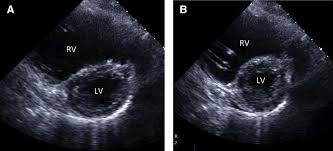

من الاشياء التي قد تحدث في التصوير التلفزيوني للقلب

توسع البطين الايمن RV dilation and dysfunction

سواءا بسبب جلطات رئويه او غيرها

ضعف في عضلة القلب الانقباضي والانبساطي بالجهة اليسرى

وغيرها من التفاصيل